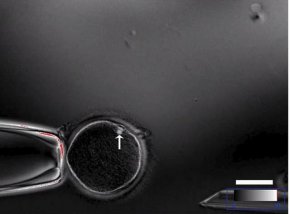

Европейският парламент (ЕП) отхвърли с голямо мнозинство клонирането на животни за храни и търговия с получени по този начин хранителни продукти, предаде АФП.

"Много е важно храните, получени от клонирани животни, да бъдат изключени" от разглеждан в момента текст за серия от нови категории храни, разрешени в ЕС, подчерта холандската депутатка от ЕП Картика Тамара Лиотард от Обединената европейска левица, която е автор на доклад по този въпрос, одобрен от ЕП. Според сондажите мнозинството от европейските граждани отхвърлят клонирането на животни за хранителни цели. Еврокомисарят по здравеопозването Андрула Василиу заяви, че не подкрепя клонирането на животни за производство на храни, но нейната позиция може да не се споделя от останалите членове на ЕК.